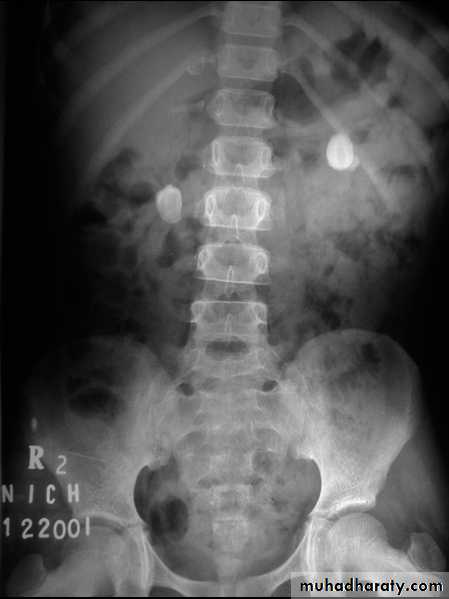

Slide 41- What is the finding in this x ray?2- Give 2 deferential diagnoses